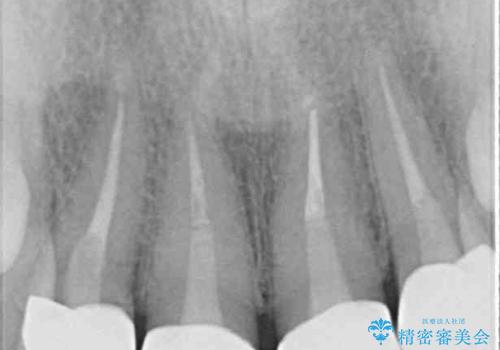

- 前歯のクラウンの変色や歯の変色を気にして来院された患者様です。

グラスファイバーを用いた土台により歯質を強化した上で、オールセラミッククラウンにて補綴することとしました。

統一感があり、歯肉ラインもきれいに整い、清潔感溢れる口元に仕上げることができました。